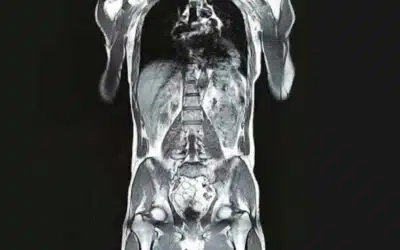

Gut/Allergy Tests & Full Body MRI

Full Body MRI Available!

Beingwell is very proud to announce its partnership with OneMRI, and are now offering full-body, no radiation MRI scans! For the best-quality, preventative health tools, we're bringing you the most competitive prices on the market to add full-body MRI scans into your...